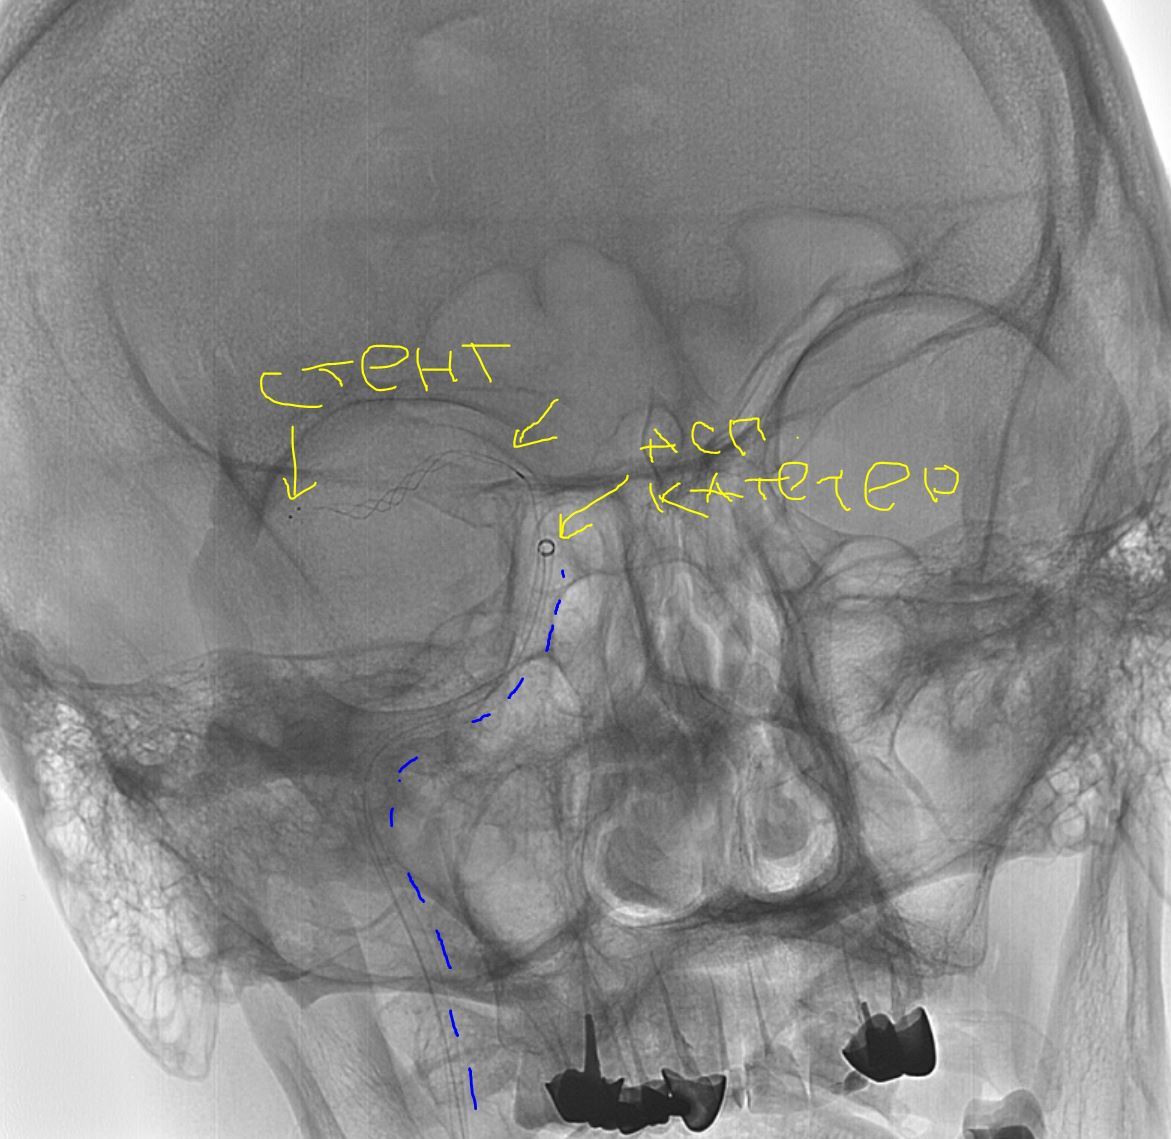

Далее гайд катетер вместо диагностики, с учетом характера поражения решаю выполнить комбинированную методику = аспирационный катетер с одновременным использованием стента ретривера (усиленная методика ВСТЭ, я ее предпочитаю). Делаю т.н. "матрешку" = в гайд аспирационник, далее микрокатетер и проводник для реканализации и заведения "микрика". Все получилось без особых усилий. После заведения микрокатетера провел стент ретривер (для извлечения тромба), раскрыл его, удалив микрик, заякорился и максимально, как мог подвел на аспирации аспирационный катетер (картинка ниже)

Завел опять ретривер, аспирационный катетер.

Четвертая попытка.

Комбинированная техника ВСТЭ: Время 23:51;Тип техники SAVE;Аспирационный катетер React 68; Стент-ретривер Trevo 3,0*20; Целевой сосуд пВСА + пСМА;Кровоток AOL исх. 0; Кровоток AOL кон. 3; Количество попыток 5; Удалено большое количество плотных красных тромбов; Осл. Нет; Результат оптимальный;